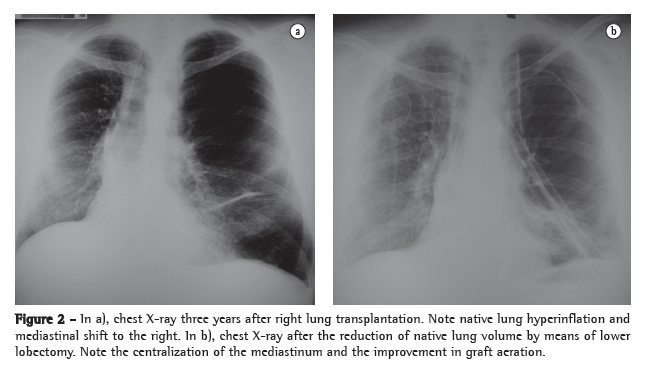

After 7 months on a waiting list, the patient underwent single right lung transplantation, in which the duration of ischemia was 210 min. Immunosuppression was performed with azathioprine, cyclosporine and methylprednisolone. The patient was referred to the ICU and remained intubated for 5 days. However, he developed respiratory failure and required reintubation. There was progressive native lung hyperinflation, with mediastinal shift and worsening of the respiratory pattern. Independent ventilation was employed but did not result in radiological or clinical improvement (Figure 1).

The patient underwent left lung volume reduction surgery to prevent compression of the graft. A linear cutting stapler was used, and multiple wedge resections were performed. Approximately 20% of the parenchyma in the lung apex was removed. The mechanical suture line was reinforced by interposing bovine ­pericardial tissue, as previously described by Cooper.(8)

There was radiological improvement, with expansion of the graft and normalization of the diaphragmatic contour, as well as improvement in pulmonary function (Figure 1). However, the patient developed dehiscence of the anastomosis of the anterior wall of the right main bronchus, together with bronchopleural fistula. The consequent empyema and sepsis led to his death on postoperative day 16.